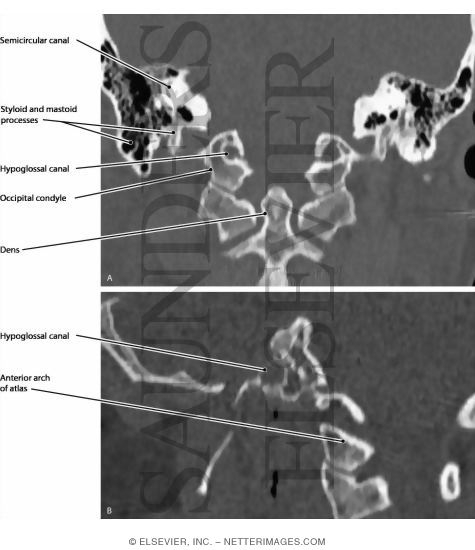

Hypoglossal Nerve Intermedullary Course

Hypoglossal Nerve Intermedullary Course

Hypoglossal Nerve (XII) and Canal

Radiology Anatomy Images : Origin of the Hypoglossal nerve in MRI Anatomy

Hypoglossal nerve leaving the hypoglossal canal, right view. hn …

Hypoglossal nerve leaving the hypoglossal canal, right view. hn …